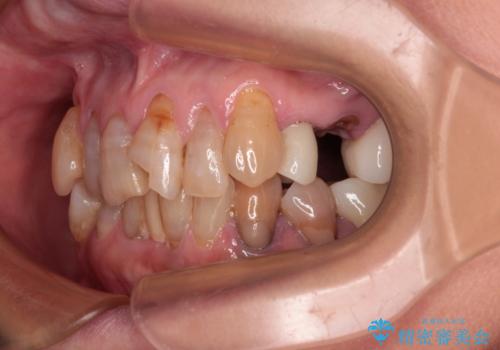

デコボコが強いため、ブリッジや残根となっている部分のスペースを利用して歯列を整え、変色や欠けている歯をオールセラミッククラウンによる補綴治療を行うこととしました。

歯肉移植などによる前歯部の歯肉ライン改善を提案しましたが、口を開けたときにほとんど見えないので気にならないとのことで、特に処置を行うことなく補綴治療を行いました。